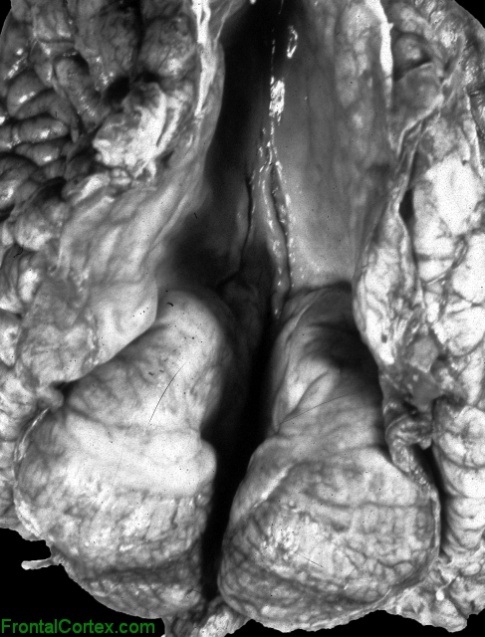

C. HIDRANENSEFALI

Pertama diperkenalkan oleh Cruveilhier pada 1829 sebagai anensefali hidrosefalik. Suatu defek otak yang berat dimana hemisfer serebral digantikan oleh kista yang bermembran yang terdiri dari membran pia-glia yang tebal. Otak yang melapisinya serta tengkorak berkembang normal.

Defek otak yang merata pada hidranensefali tampak pada teritori arteria cerebral anterior dan media, jadi lobus frontal, parietal, temporal dan oksipital anterior. Ganglia basal, batang otak dan serebelum biasanya normal. Defek berkisar dari kasus yang berat, dimana hanya bagian dari lobus temporal dan oksipital serta ganglia basal yang ada, hingga defek terbatas pada teritori arteria serebral media dan mungkin lebih baik disebut porensefali. Terkadang hidranensefali unilateral ditemukan. Hidranensefali simpel tidak bersamaan dengan hidrosefalus; jenis hidranensefali lainnya bersamaan dengan hidrosefalus akibat stenosis akuaduktal.

Insidens hidranensefali sekitar 0.2 persen dari neonatus. Lahir mati atau mati usia bayi muda sering pada kasus yang berat. Mikrogiria sering ditemukan pada tepi hemisfer serebral, dan korteks hemisfer sisanya sering memperlihatkan empat lapisan yang mengandung banyak neuron yang immatur. Ventrikel lateral tidak ada, tapi ventrikel ketiga terkadang dijumpai. Pleksus khoroid biasanya ada. Pons, medulla, serebelum, tentorium, dan saraf otak dijumpai, namun sering kecil abnormal.

Patogenesis hidranensefali belum pasti. Infeksi maternal, irradiasi, usaha menginduksi aborsi, anemia, intoksikasi karbon monoksida, leher terjerat tali pusat, dan anoksia fetal dilaporkan sebagai penyebab. Hipotesa yang paling umum adalah oklusi porsi supraklinoid arteria karotid internal in utero dengan infarksi serebral progresif; patogenik mekanisme ini dipastikan secara percobaan, penelitian patologis dan klinis. Anomali dipercaya berkembang setelah minggu keenam kehidupan fetal, karena arkhitektur otak, kecuali porsi yang defektif, adalah normal.